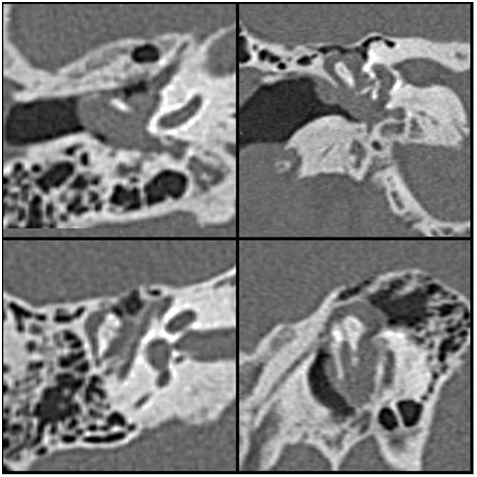

In October 2010, a 48-year old man presented at our otorhinolaryngology department with a 3-month history of right hearing loss, tinnitus and aural fullness. The otoscopy revealed a gray-white nonpulsatile poster superior retro tympanic mass with intact tympanic membrane (Figure 1). The hearing test confirmed a mild conductive hearing loss. A high-resolution temporal CT showed a well-circumscribed soft-tissue mass in the epitympanic area that was embedded in the ossicles without evidence of bone erosion (Figure 2). MRI revealed a middle ear mass with low intensity on T1weighted images, high intensity on T2-weighted images, and enhancement after administration of gadolinium.

Figure 2 High resolution temporal CT shows a soft-tissue epitympanic mass embedded in the ossicles.

High-resolution temporal CT typically shows a relatively well-circumscribed soft tissue-attenuation enhancing mass without evidence of bone erosion. The MRI characteristics of the middle ear adenoma are low-to-intermediate intensity on T1weighted images, high intensity on T2-weighted images, and enhancement after administration of gadolinium.4